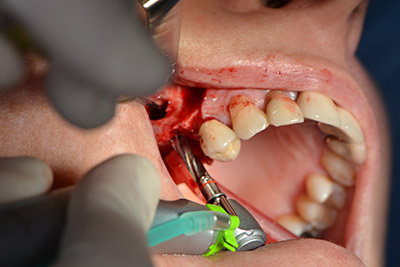

The next step was the sinus floor elevation with simultaneous implantation. The Implantmed also had a presetting at the first position for the buccal fenestration of the maxillary sinus wall.

The fenestration was prepared at 35,000 rpm and then the nasal mucosa were prepared in the cranial direction (Fig. 13 to 14).

preparation of the nasal mucosa

Image 13

Inclined drilling

Image 14